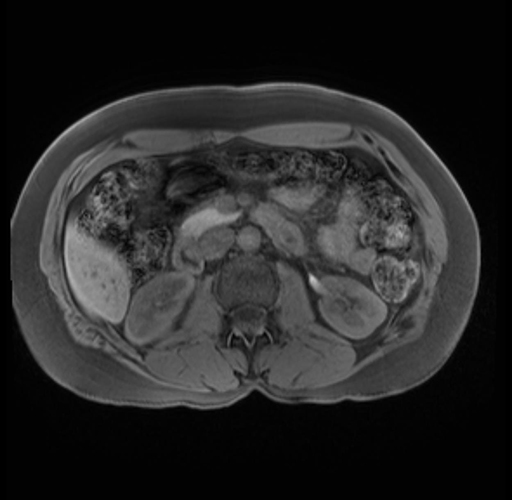

Imaging Analysis

Look through the patient's CT scan to identify any areas of concern for the necessary procedure.

Based on your CT findings, which issue(s) are present and would give reason for "planned slowing down moment(s)" in this case?